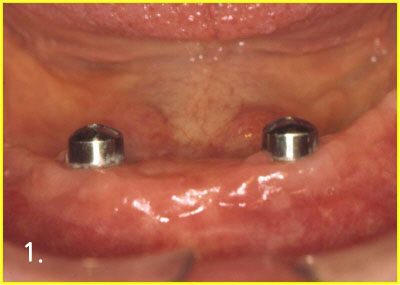

Implant Over-Denture

Placing implant for over-denture

Engaging attachment to implant

Engaging attachment inside denture

After engaging attachment with implant and denture. Now, patient can feel comfortable with denture much more than before